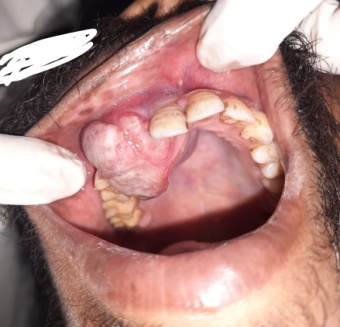

On examination, there was obvious extra oral asymmetry of the face ([Figure 1]A). The right nasolabial fold was obliterated ([Figure 1]B). Intra orally, there was a fleshy mass of the right upper alveolar ridge in the lateral incisor and canine region. Both the teeth had exfoliated. The lesion extended towards the palate as well as Buccal vestibule and showed rapid growth with a size of more than 3cm by 4cm. There was no ulcerated lesion or obvious granular surface or keratinisation ([Figure 2]).

After routine blood examinations, Incisional biopsy was done from the lesion under local anaesthesia. A mucosa covered irregular piece of tissue was sent for histopathology. There was no healing of the biopsy wound ([Figure 4]).